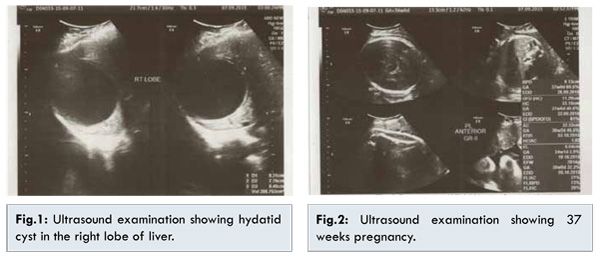

The patient was a primigravida 25 years old, resident of northern India. This was a spontaneous pregnancy. The first trimester of pregnancy was uneventful and all routine investigations were normal. The patient had taken folic acid, iron and calcium. At 24 weeks gestation, the patient had pain on right upper abdomen which subsided after 4-5 hours. She experienced a similar attack of pain 10 days after. On examination vitals were stable. However, ultrasound  abdomen revealed an exophytic cyst in the right lobe of liver (8 cm) with no calcification and a single live fetus with growth corresponding to 25 weeks of pregnancy. A provisional diagnosis of hydatid cyst was made which was supported by a positive anti-echinococcal antibody testing by ELISA (IgG). An opinion from the surgeon was sought. A conservative approach to the hydatid cyst was decided because of the fear of preterm labour and the risk of severe anaphylaxis during pregnancy. The patient was put on albendazole in a dose of 400 mg once a day. Serial liver functions tests were done which were normal. The patient was monitored regularly.

The patient went into spontaneous labour at 38 weeks. Ultrasound examination showed 8 cms hydatid cyst along with 38 weeks pregnancy [Fig.1,2]. She received prophylaxis (antihistaminics, steroids) during labour. She delivered a 3 kilogram healthy baby. Placenta did not reveal any abnormality on gross examination. Anti-helminthic medication was continued during post-partum period. Patient was then referred to s

urgical department for removal of the cyst and further treatment.